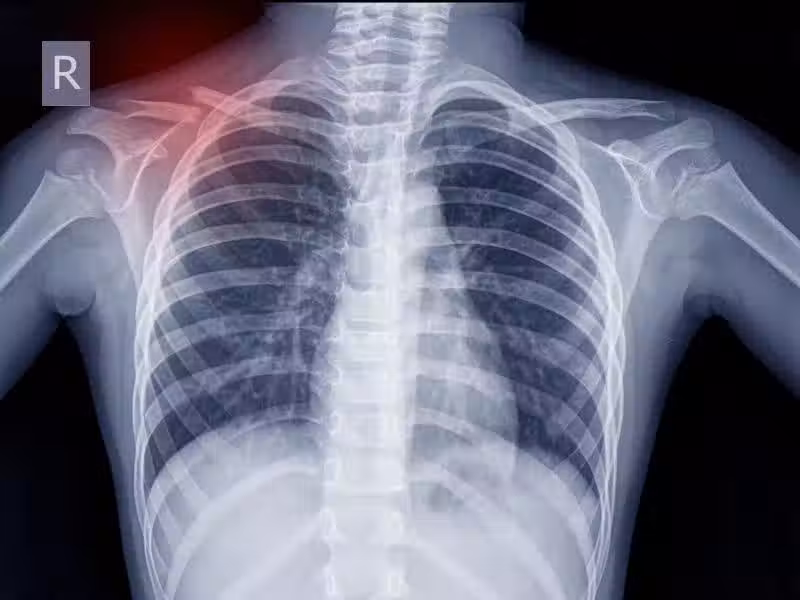

肺癌開始時!四肢可能會有「3個跡象」 醫生勸:哪怕「有了1個」都應該重視!

肺癌開始時!四肢可能會有「3個跡象」 醫生勸:哪怕「有了1個」都應該重視

其實和多數癌症一樣,肺癌在早期階段,症狀也不明顯、不典型。

很容易和其他呼吸系統疾病相混淆,等到症狀嚴重或者自行用藥無效來醫院檢查時,往往都已經發展至中晚期。

當然,肺癌開始時,並非一點信號都沒有,只是患者容易忽視。 如果四肢有3個跡象,哪怕僅有1個,也應該給予重視!